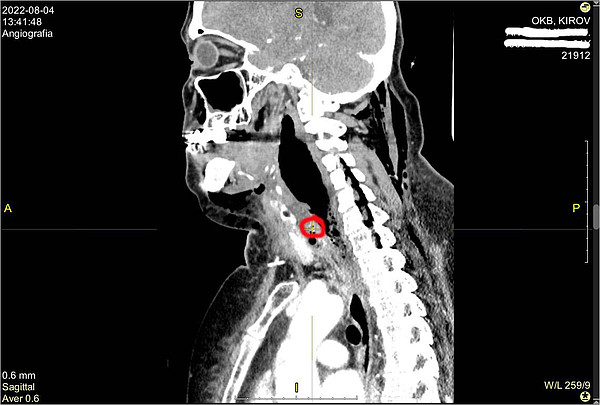

IMG_5289КТ пациентки1

КТ пациентки1.